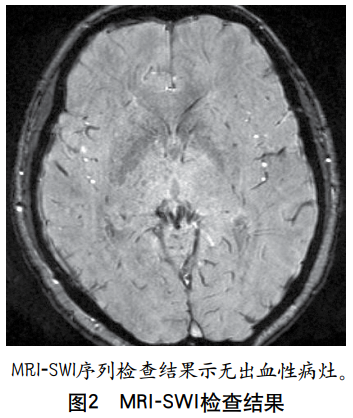

摘要:非酮症高血糖(non-ketotic hyperglycemia,NKH)相关脑病在临床上较为罕见,其表现形式多样,易被误诊或漏诊。本文报道1例以卒中样发作为主要表现的青年NKH相关脑病患者,详细分析其临床表现、影像学特征及诊疗经过,利用多模态MRI技术清晰呈现其病变特点,并总结NKH相关脑病的核心影像学特征及潜在病理生理机制,以期为疾病诊断提供可靠的影像学依据。1 病例介绍患者男性,36岁